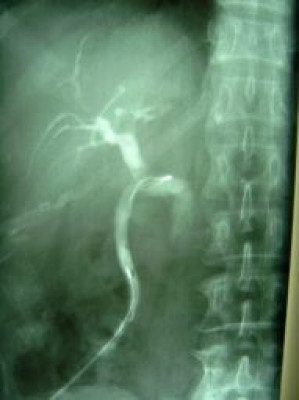

Extracción percutánea de cálculo de coledoco

Envíado por Dr. Carlos Miguel Zavaleta Consuegra